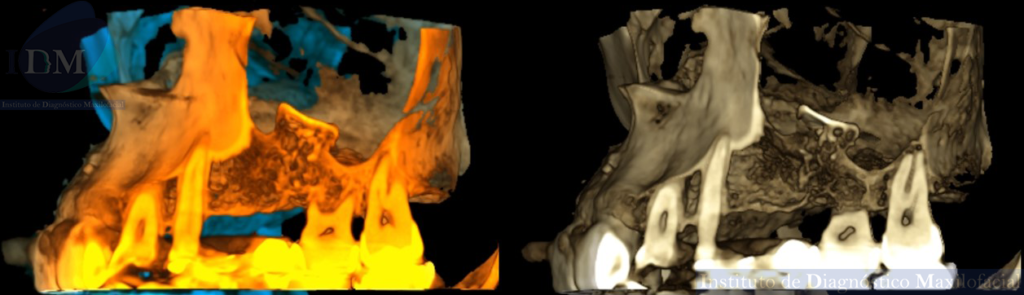

A la evaluación de la tomografía computarizada de haz cónico (TCHC) en los cortes axiales, transaxiales y en la reconstrucción 3D se observa una estructura ovalada hiperdensa heterogénea con contenidos mixtos irregulares localizada en piso del seno maxilar izquierdo con extensión hacia el antro sinusal. Además, en las imágenes tangenciales se observa la presencia de un antrolito adyacente a nivel de la pieza 26.

RECONSTRUCCIÓN 3D